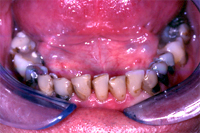

Die Situation eines 67 Jahre alten Patienten, dem ich im Verlaufe einer Zahnsanierung alle alten Amalgamfüllungen (s. Amalgamersatz) im Unterkiefer durch Komposite ersetzte, ist in den Abb. 1 vor und in Abb. 2 nach der Behandlung zu sehen. Möglich war dies nur dank der Full Bond Technik.